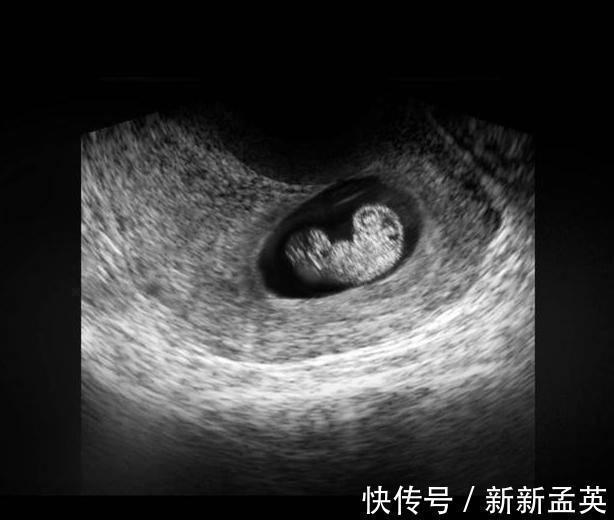

在上图可见是个双胎妊娠,胎儿具有一个很大的头,和身材很不对称,是不是跟出生后的胎宝宝有点像了?其实此时的头部比例更悬殊,宝宝的额面部器官发育很明显,心脏也开始了跳动,出现了胎心,此时做B超,可见胎心胎芽。